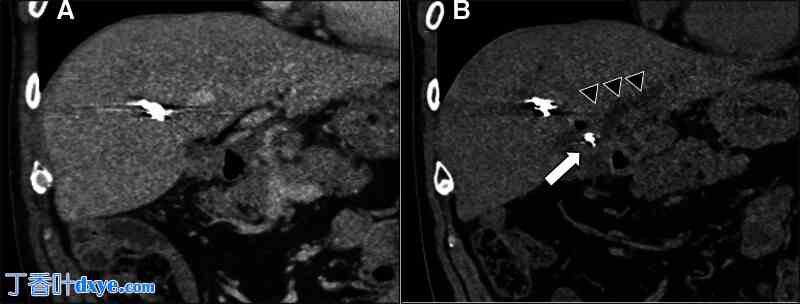

根据这些结果,进行了双气囊内窥镜检查 (DBE)。 DBE 显示在吻合口处确定了以线圈为中心的结石 (图 3A)。 同时无法取出结石,因此放置了塑料支架 (图 3B)。 在第二次 DBE 期间,使用 8 毫米球囊扩张吻合口,然后使用破碎篮将结石碎裂 (图 4A),成功取出结石。 使用篮钳取出结石时确认线圈包含在内 (图 4B)。

图 3。

双气囊内窥镜检查结果。(A)在胆管空肠吻合口处观察到带有线圈的半透明物,大小为 15 毫米。(B)由于取石困难,放置了塑料支架。

图 4。

进行了第二次 ERC。(A)使用碎石机抓取器将结石碎裂。(B)成功取出了带有线圈的结石。